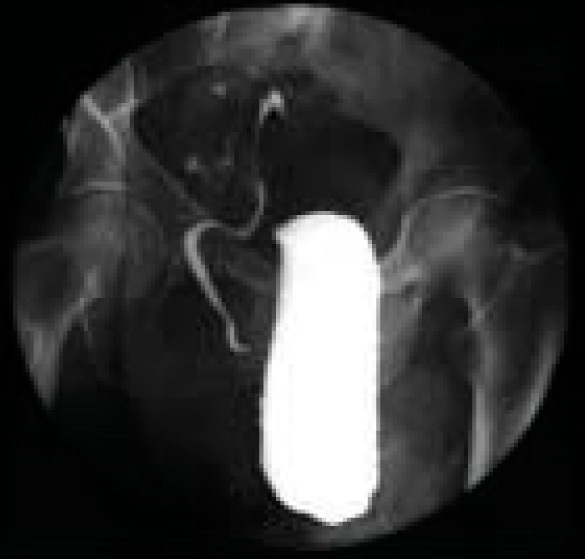

Cystographie. Volumineuse hernie contenant la vessie chez un patient transplanté hépatique et rénal (Photo : centre de chirurgie viscérale et de transplantation [Pr Ph. Wolf], CHU Hautepierre, Strasbourg). Voir : Rohr S, Steinmetz JP, Brigand C, Meyer C. Diagnostic et complications des hernies de l'aine. Rev Prat 2003;53(15):1645-50.